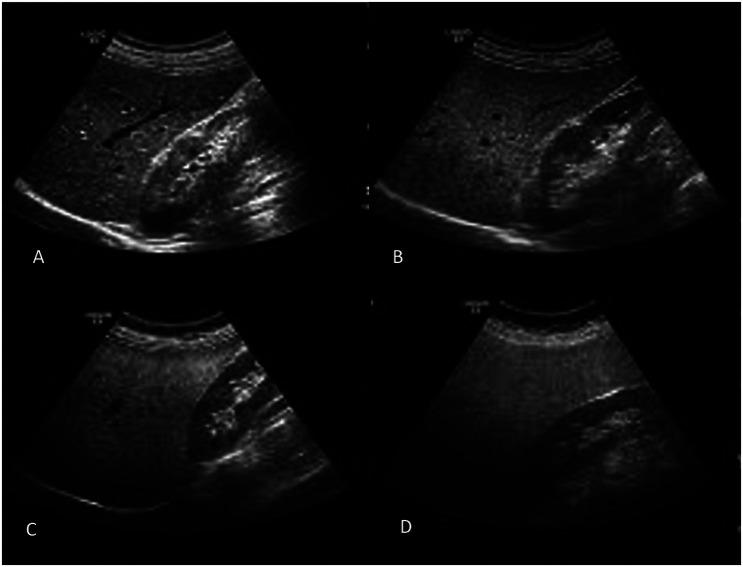

This cross-sectional study was designed to evaluate the relationship between cholecystectomy and MAFLD. Metabolic dysfunction-associated fatty liver disease was defined by the presence of hepatic steatosis in combination with any of the following conditions: diabetes mellitus (fasting plasma glucose ≥126 mg/dL), overweight (body mass index (BMI) ≥25 kg/m2), or metabolic dysregulation.

A total of 163 participants with BMI ≥25 kg/m2, including consecutive cholecystectomized (N = 83) and non-cholecystectomized (N = 80) subjects, were included. The prevalence of MAFLD was found in 64 out of 83 (77.1%) cholecystectomized patients and in 30 out of 80 (37.5%) non-cholecystectomized subjects (P < .001). When age, gender, BMI, exercise habits, hypertension, diabetes mellitus, and cholecystectomy status were included in regression analyses, we found that only BMI [odds ratio (OR) = 1.155 (95% CI: 1.040-1.283)] and cholecystectomy [OR = 4.540 (95% CI: 2.200-9.370)] were independently associated with MAFLD (both P < .01). ROC analysis identified 10 years as the cut-off, with MAFLD risk being 2.7-7.3 times higher in patients with cholecystectomy for ≤10 and >10 years.

本横断面研究旨在评估胆囊切除术与MAFLD之间的关系。代谢功能障碍相关脂肪性肝病的定义为存在肝脂肪变性并伴有以下任何一种情况:糖尿病(空腹血糖≥126mg/dL)、超重(体重指数(BMI)≥25kg/m²)或代谢失调。

共有163名BMI≥25kg/m²的参与者,包括连续接受胆囊切除术的患者(N = 83)和未接受胆囊切除术的患者(N = 80)。在83名接受胆囊切除术的患者中,有64名(77.1%)被发现患有MAFLD,而在80名未接受胆囊切除术的患者中,有30名(37.5%)患有MAFLD(P <.001)。当将年龄、性别、BMI、运动习惯、高血压、糖尿病和胆囊切除术状态纳入回归分析时,我们发现只有BMI[比值比(OR)= 1.155(95%置信区间:1.040 - 1.283)]和胆囊切除术[OR = 4.540(95%置信区间:2.200 - 9.370)]与MAFLD独立相关(两者P <.01)。ROC分析确定10年为临界值,胆囊切除术≤10年和>10年的患者患MAFLD的风险分别高出2.7 - 7.3倍。